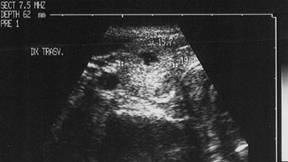

Lob drept, proiectie trasversale si longitudinala.

Femeie de 23 ani. Sub capsula, un mic nodul, de 12x16x19mm (1,8 cc), hipoecogen, neomogen, cu margini ne definite. Examen citologic prin citoaspiratie: carcinom papilar confirmat si histologic.

Lob drept, proiectie trasversala si longitudinala.